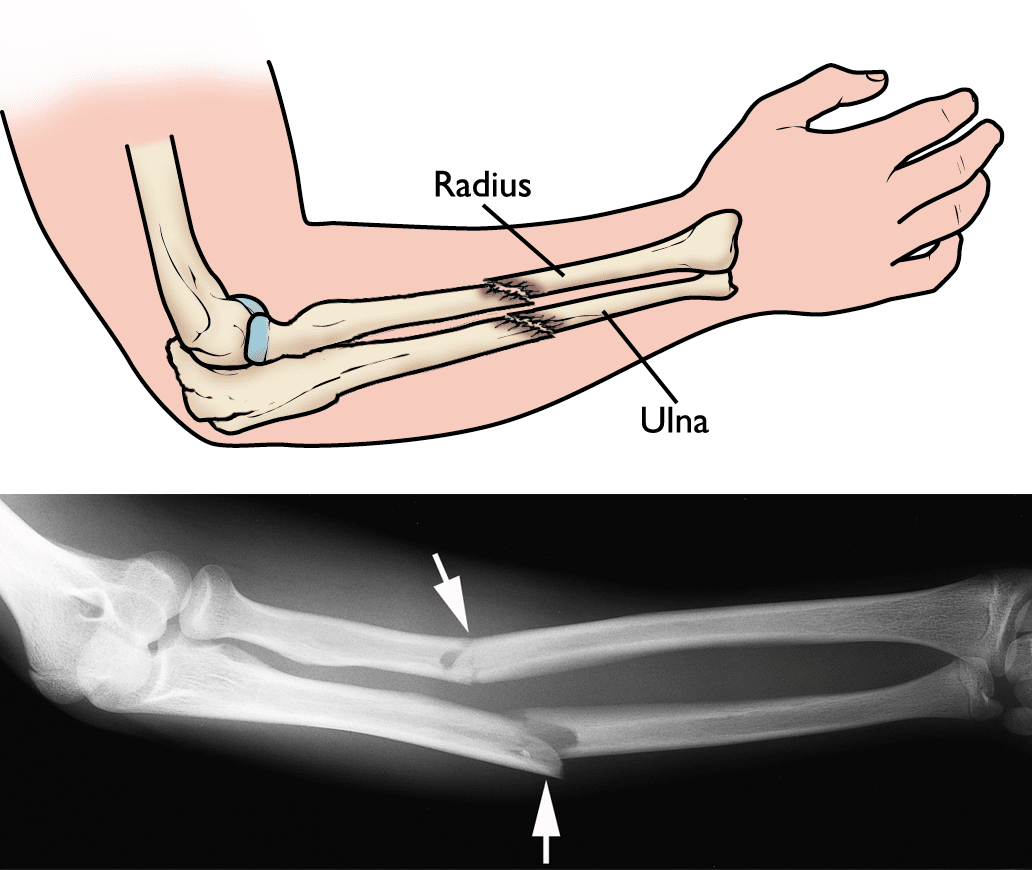

Fractures of both the radius and ulna.

Illustration and X-ray showing fractures of both the radius and ulna.

The forearm is made up of two bones: the radius and ulna. In most cases of adult forearm fractures, both bones are broken.

Because of the strong force required to break the radius or ulna in the middle of the bone, it is more common for adults to break both bones during a forearm injury. When only one bone in the forearm is broken, it is typically the ulna — usually as a result of a direct blow to the outside of your arm, such as when you have it raised in self-defense.